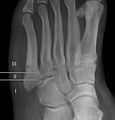

Cropped version of Jonesfracture.jpg

Jones fracture as seen on Xray

A Jones fracture is a break between the base and middle part of the fifth metatarsal of the foot.[8] It results in pain near the midportion of the foot on the outside.[2] There may also be bruising and difficulty walking.[3] Onset is generally sudden.[4]

The fracture typically occurs when the toes are pointed and the foot bends inwards.[6][2] This movement may occur when changing direction while the heel is off the ground such in dancing, tennis, or basketball.[9][10] Diagnosis is generally suspected based on symptoms and confirmed with X-rays.[3]

Diagnostic x-rays include anteroposterior, oblique, and lateral views and should be made with the foot in full flexion.

For several reasons, a Jones fracture may not unite. The diaphyseal bone (zone II), where the fracture occurs, is an area of potentially poor blood supply, existing in a watershed area between two blood supplies. This may compromise healing. In addition, there are various tendons, including the peroneus brevis and fibularis tertius, and two small muscles attached to the bone. These may pull the fracture apart and prevent healing.

Zones I and III have been associated with relatively guaranteed union and this union has taken place with only limited restriction of activity combined with early immobilization. On the other hand, zone II has been associated with either delayed or non-union and, consequently, it has been generally agreed that fractures in this area should be considered for some form of internal immobilization, such as internal screw fixation.

These zones can be identified anatomically and on x-ray adding to the clinical usefulness of this classification.[18] Surgical intervention is not, by itself, a guarantee of cure and has its own complication rate. Other reviews of the literature have concluded that conservative, non-operative, treatment is an acceptable option for the non-athlete.[19]